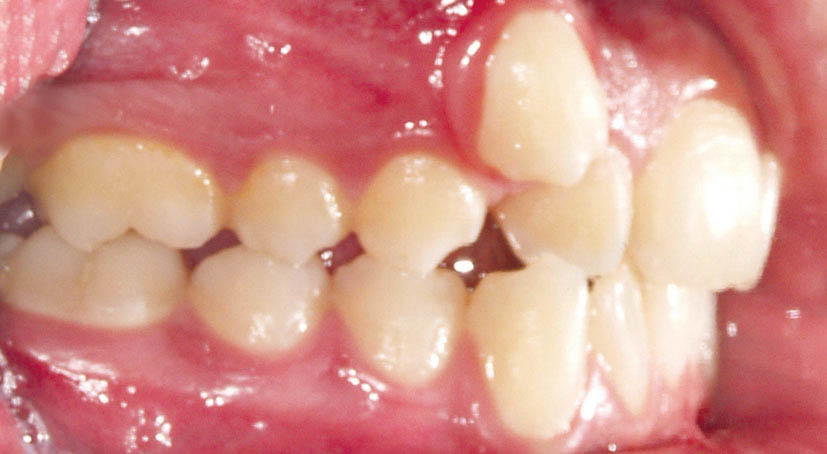

در یک اکلوژن 3.5mm کلاسII (شکل 123-2) وقتی پرمولر پایین کشیده شود خلفیهای پایین حدود نیم کاسپ (3.5mm) جلو میآیند (شکل 124-2)، پس خلفیهای بالا اصلاً نباید جلو بیایند تا رابطه کلاسI حفظ شود (شکل 125-2). بنابراین از مینی اسکرو استفاده کنید و باید تمام نیروها را به آن اعمال کنید.

شکل 123-2: اکلوژن نیم کاسپ کلاسII